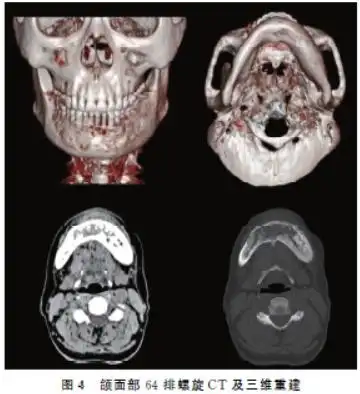

颌骨牙源性硬化性癌的影像学特征分析